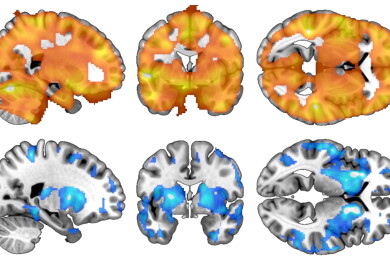

In addition to people who had suffered a stroke, the researchers used magnetic resonance imaging (MRI) to scan the brains of 20 individuals with developmental stuttering. In these individuals, the stuttering was associated with structural changes in the nodes of the brain network originally identified in relation to causal stroke lesions – the greater the changes, the more severe the stuttering. This finding suggests that stuttering is caused by a common brain network, regardless of the aetiology (developmental or neurological).

The key nodes of the network identified by the researchers were putamen, amygdala and claustrum located deep within the brain, and the connections between them.

Red: the central nodes of the brain network identified based on stroke lesions causing stuttering

Blue: structural changes correlated with the severity of persistent developmental stuttering

ASt=amygdalostrital transition zone. Pu=Putamen. Cl=Claustrum.

"These findings explain well-known features of stuttering, such as the motor difficulties in speech production and the significant variability in stuttering severity across emotional states. As major nuclei in the brain, the putamen regulates motor function and the amygdala regulates emotions. The claustrum, in turn, acts as a node for several brain networks and relays information between them,” explains Joutsa.